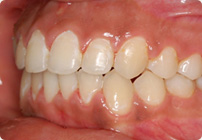

Femenino

Antes

Despues

Caso: 12 años

Adolescente: Clase II

Dental Maxilar Protrusion

Extract U4’s/L5’s

4 series de alambres:

.016″, 022″, .0215″ x .028″, .019″ x .025″ Trenzado

Elástico clase 2 2oz. TP amarillos y verdes

Retenedores: Interior Fijo de TMA y Hawley en superior

Tiempo de tratamiento: 15 Visitas